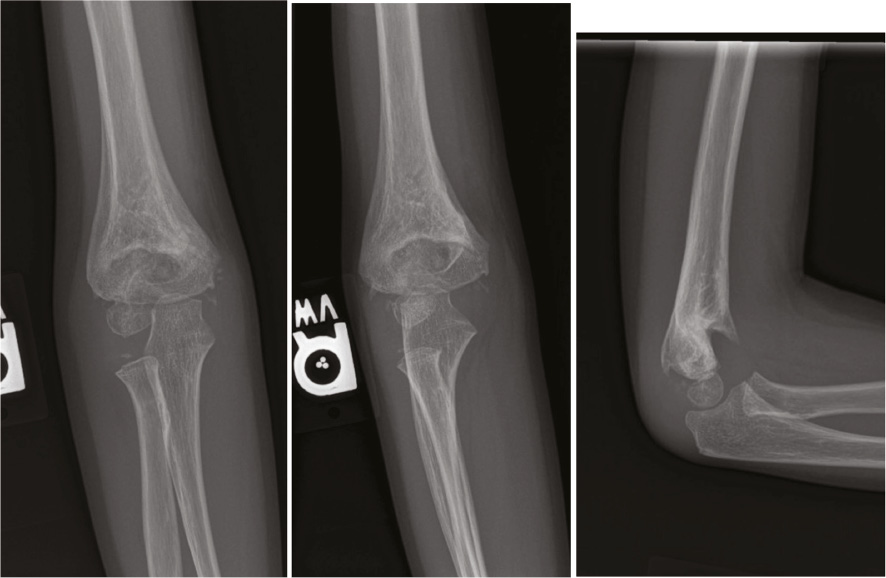

From www.schreibermd.com

Kid's Elbow Fracture Raleigh Hand Surgery — Joseph J. Schreiber, MD Pin Fixation Of Supracondylar Fractures Without such good stability, or with the distal fragment anterior to the shaft (a flexion type supracondylar fracture), the reduction and. Supracondylar humerus fractures are treated within 24 h from trauma by 33.2% of respondents. Is lateral pin fixation for displaced supracondylar fractures of the humerus better than crossed pins in children? Fracture type (72.3%), surgeon experience, and (71.2%) are. Pin Fixation Of Supracondylar Fractures.